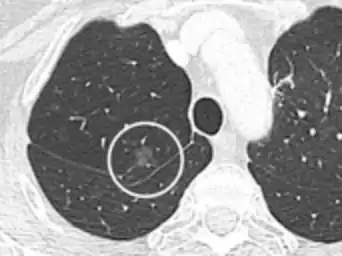

A "notch sign".[9]

- Margin morphology: a spiculated margin is a risk factor for cancer.[8] Benign causes tend to have a well defined border, whereas lobulated lesions or those with an irregular margin extending into the neighbouring tissue tend to be malignant.[10] In particular, spiculations are highly predictive of malignancy with a positive predictive value up to 90%.[9] Also, a "notch sign", which is an abrupt indentation of the nodule, increases the risk of cancer, but may also be found in granulomatous diseases.[9]